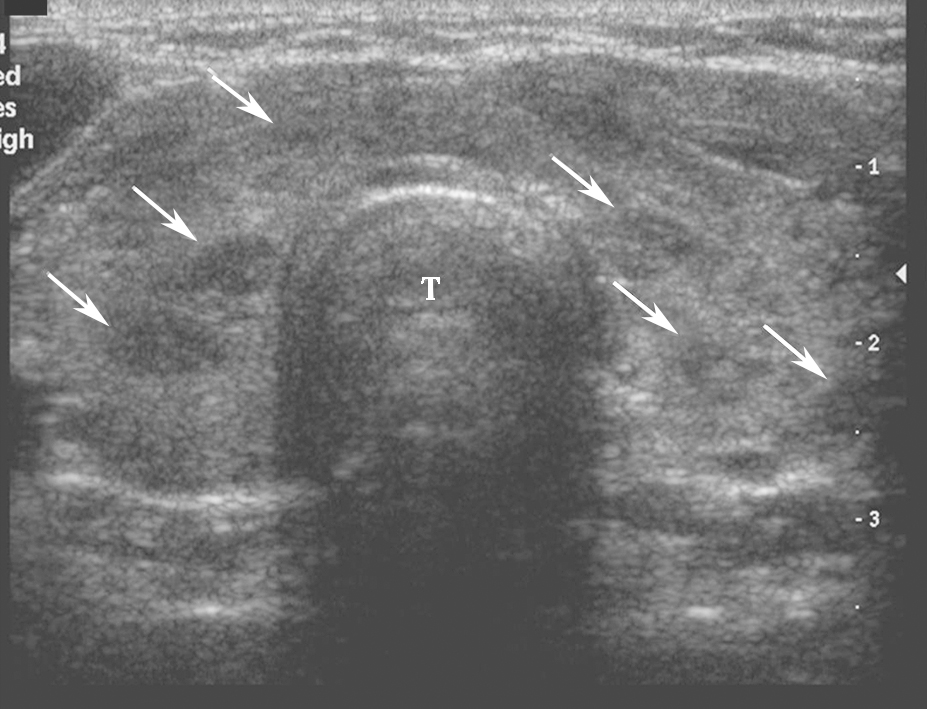

桥本甲状腺炎超声表现为甲状腺弥漫性增大,以前后径改变最为明显,峡部明显增厚。腺体包膜清晰完整,回声弥漫性不均减低(图2)。腺体内可见多个由淋巴组织、残余滤泡和上皮组织形成的无占位效应的低回声小结节。腺体广泛纤维化后体积可缩小。甲状腺下极附近淋巴结增大对于诊断有参考价值。

图2颈部正中横切面:甲状腺腺体回声不均匀,峡部增厚,可见多个无占位效应的低回声小结节(箭头所示),T:气管